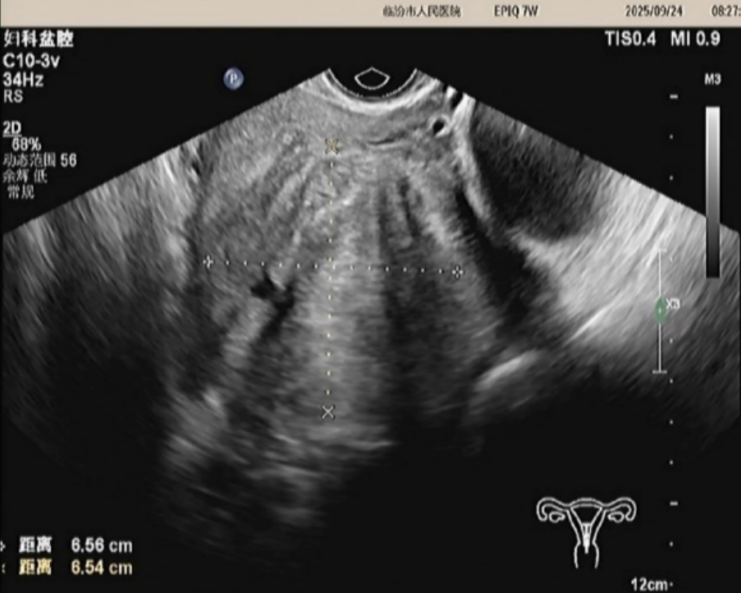

经过术前评估,完善相关检查后,患者于2025年9月25日接受高强度聚焦超声(HIFU)治疗,手术过程顺利,术后无不适,第二天出院。目前术后3个月,正常行经2次,痛经症状明显好转,经量减少,通过术前术后的超声影像学的对比,患者子宫腺肌瘤瘤体的大小及子宫的大小较前明显缩小,瘤体的大小由术前的6.6*6.6cm缩小为5.3*3.3cm,子宫的大小由术前的10*9cm缩小为8*7cm。预计随着时间的时间的推移,治疗效果将更加明显。

治疗前